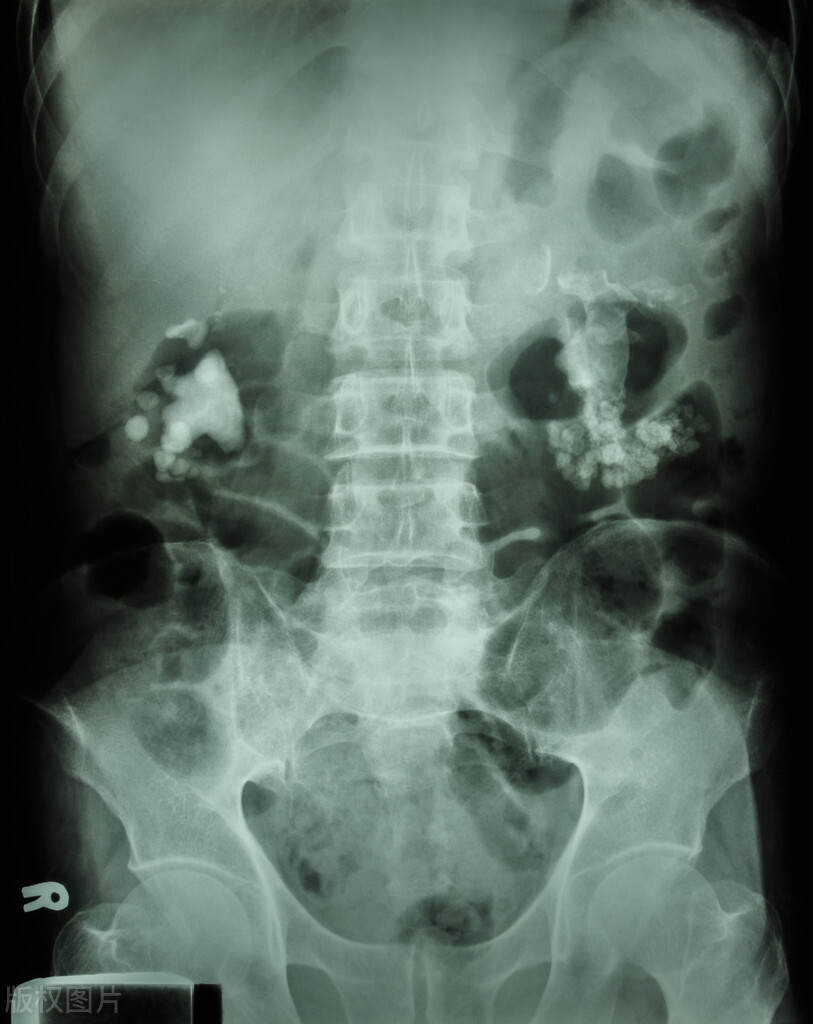

2022年5月4日晚上,何某因左腰腹部疼痛不适,到A医院住院治疗,入院诊断:1、左肾盂积水伴有肾和输尿管结合梗阻;2、左肾周感染;3、右肾结合;4、高脂血症;5、肾功能不全;6、左肾囊肿;7、胆囊结合;8、肝钙化灶。

2022年5月5日,在全身麻醉下为何某行经尿道左侧软性输尿管镜钬激光碎石取石术+左侧输尿管支架置入术,术中发现肾盂及结合有脓苔覆盖,加用5%葡萄糖注射液500ml+阿米卡星注射液0.4g静滴,肾盂下盏结合软镜因取石角度限制,取石困难,告知患者家属手术情况,患者家属了解病情,同意中转行左肾经皮肾镜取石术,后行经皮肾镜穿刺时,发现何某血压降低至78/38mmHg,心率136次/分。